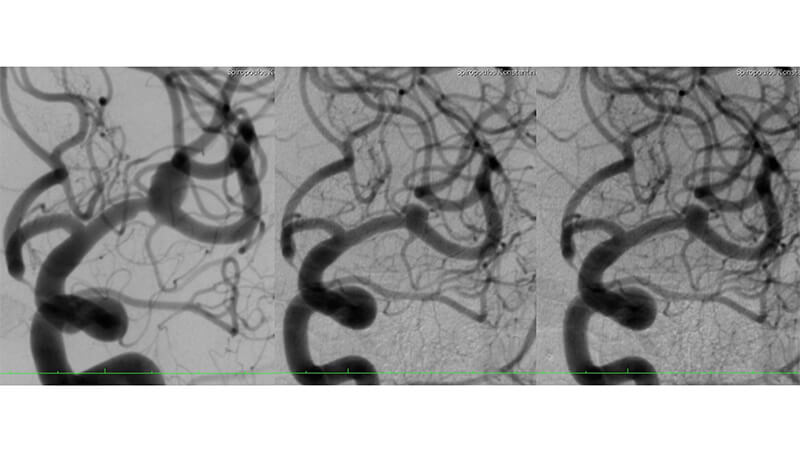

Εικόνα 1: Αγγειογραφία της αριστερής έσω καρωτίδος: Διακρίνεται μη ραγέν ανεύρυσμα του διχασμού της αριστερής μέσης εγκεφαλικής αρτηρίας.

Από την βάση του ανευρυσματικού σάκκου φαίνεται να εκφύεται μετωπιαίος κλάδος. Αμέσως πριν το ανεύρυσμα, στο τελικό Μ1 τμήμα, ελέγχεται τοπική στένωση της μέσης εγκεφαλικής αρτηρίας.